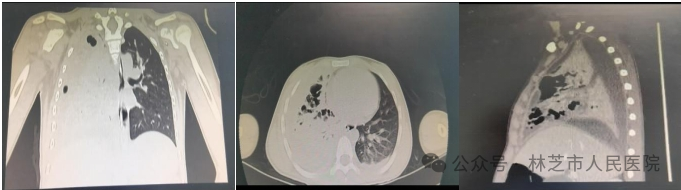

图片

▲术后第12天复查胸部CT,右肺病变基本吸收恢复